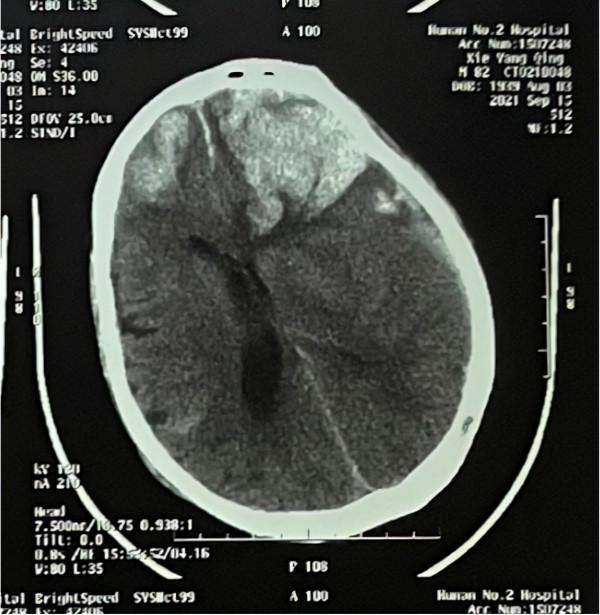

82歲的張嗲(化名),身體健朗,每天堅持在南郊公園晨練。近日,張嗲在晨練過程中突然暈倒在地,嘔吐,神志不清,在朋友的幫助下,立即送往湖南省腦科醫院(湖南省第二人民醫院)神經外科二病區進行救治,入院診斷:創傷性硬膜下血腫(左側額、頂、顳部)、腦內血腫(雙側額葉)、蛛網膜下腔出血。

入院後的張嗲病情繼續惡化,神志昏迷,瞳孔散大,形成腦疝,隨時可能危及生命,醫生建議手術治療。但患者年齡大,有長期服用阿司匹林病史,手術風險極大。

經過神經外科二病區醫生團隊全方位地進行術前評估,手術很順利,清除了顱內血腫。目前張嗲人已清醒,四肢可以活動,在醫院仍繼續治療。